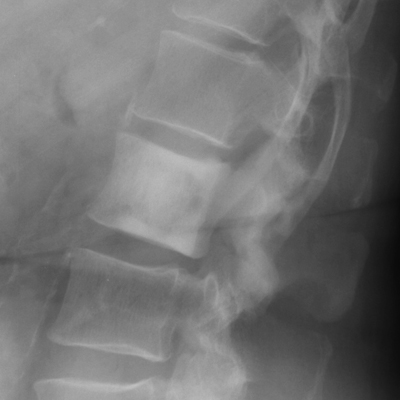

A uniformly white vertebra with no abnormality of its contour or adjacent disks. The vertebra stands out against the adjacent normal, or darker, vertebral bodies. While the list of possible etiologies of ivory vertebrae is extensive, the most common causes of ivory vertebrae are typically metastatic disease, and Paget’s. A-B. Metastatic breast cancer. C-D. Paget's disease.

Lateral lumbar spine - Click on the image for a larger versionAAP lumbar spine - Click on the image for a larger versionBIvory Vertebra - Click on the image for a larger versionCIvory Vertebra - Click on the image for a larger versionD